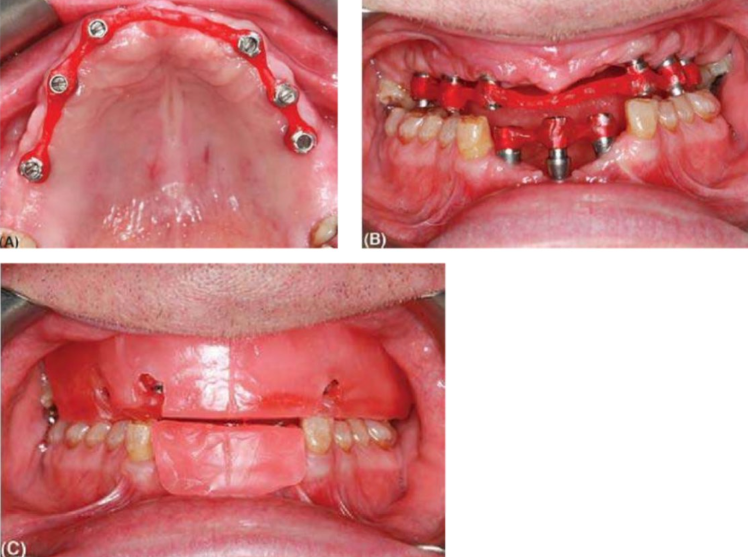

- Trước khi làm khung sườn. Các ống bằng vàng (gold cylinder) được liên kết với nhau bằng một vật liệu cứng như nhựa composite trong labo.

(A) Một khung bằng nhựa (sản phẩm Duralay) được thử để xác định vị trí của các implant và mẫu toàn hàm. (B) Thủ khung nhựa trên và dưới. (C) Sáp cắn đặt trên khung nhựa tạo ra một nền vững chắc để ghi dấu khớp cắn.

- Độ chính xác của việc lấy dấu có thể được kiểm tra bằng cách đặt cái này trong miệng. Không nên có sự dịch chuyển của khung khi vặn chặt ở hai đầu và kết nối nhựa thường sẽ bị gãy nếu khung không khít sát. Nếu điều này xảy ra, tốt nhất nên lấy dấu lại. Các ống bằng vàng nối với nhau có thể được sử dụng cho việc ghi khớp cắn bằng cách gắn một vành sáp và chúng cũng có thể hỗ trợ việc thử răng nếu cần thiết.